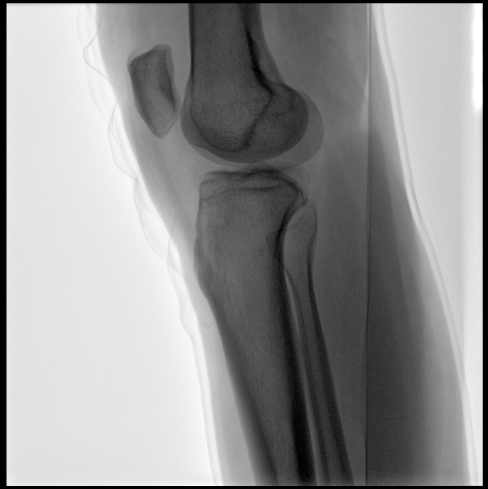

平板尺寸升級 呈現(xiàn)更多解剖細節(jié)

采用30CM×30CM大尺寸動態(tài)平板探測器,成像面積較傳統(tǒng)平板探測器大幅提升。

圖像清晰細膩

高清像素,低信噪比,細小的組織結構也可以清晰顯示。

Clinical picture

臨床圖片